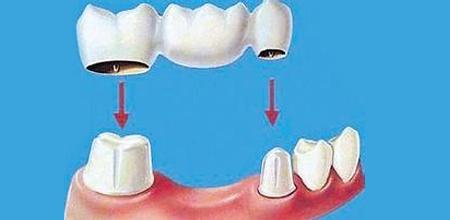

固定橋修復

固定橋的結構就像是一座橋梁,缺牙間隙部分是橋梁的身體,缺牙間隙兩邊的健康牙齒(牙基)是兩個橋頭(見上圖)。在牙齒修復完成之后,缺失的牙齒就和它前后兩顆牙齒連接成了一個整體。